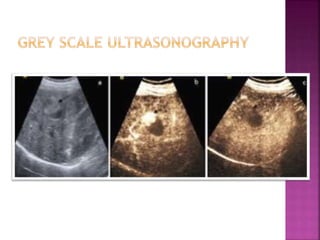

 A mode-amplitude mode-not in use

 B mode-brightness mode-producing different

echogenicity

 Grey scale